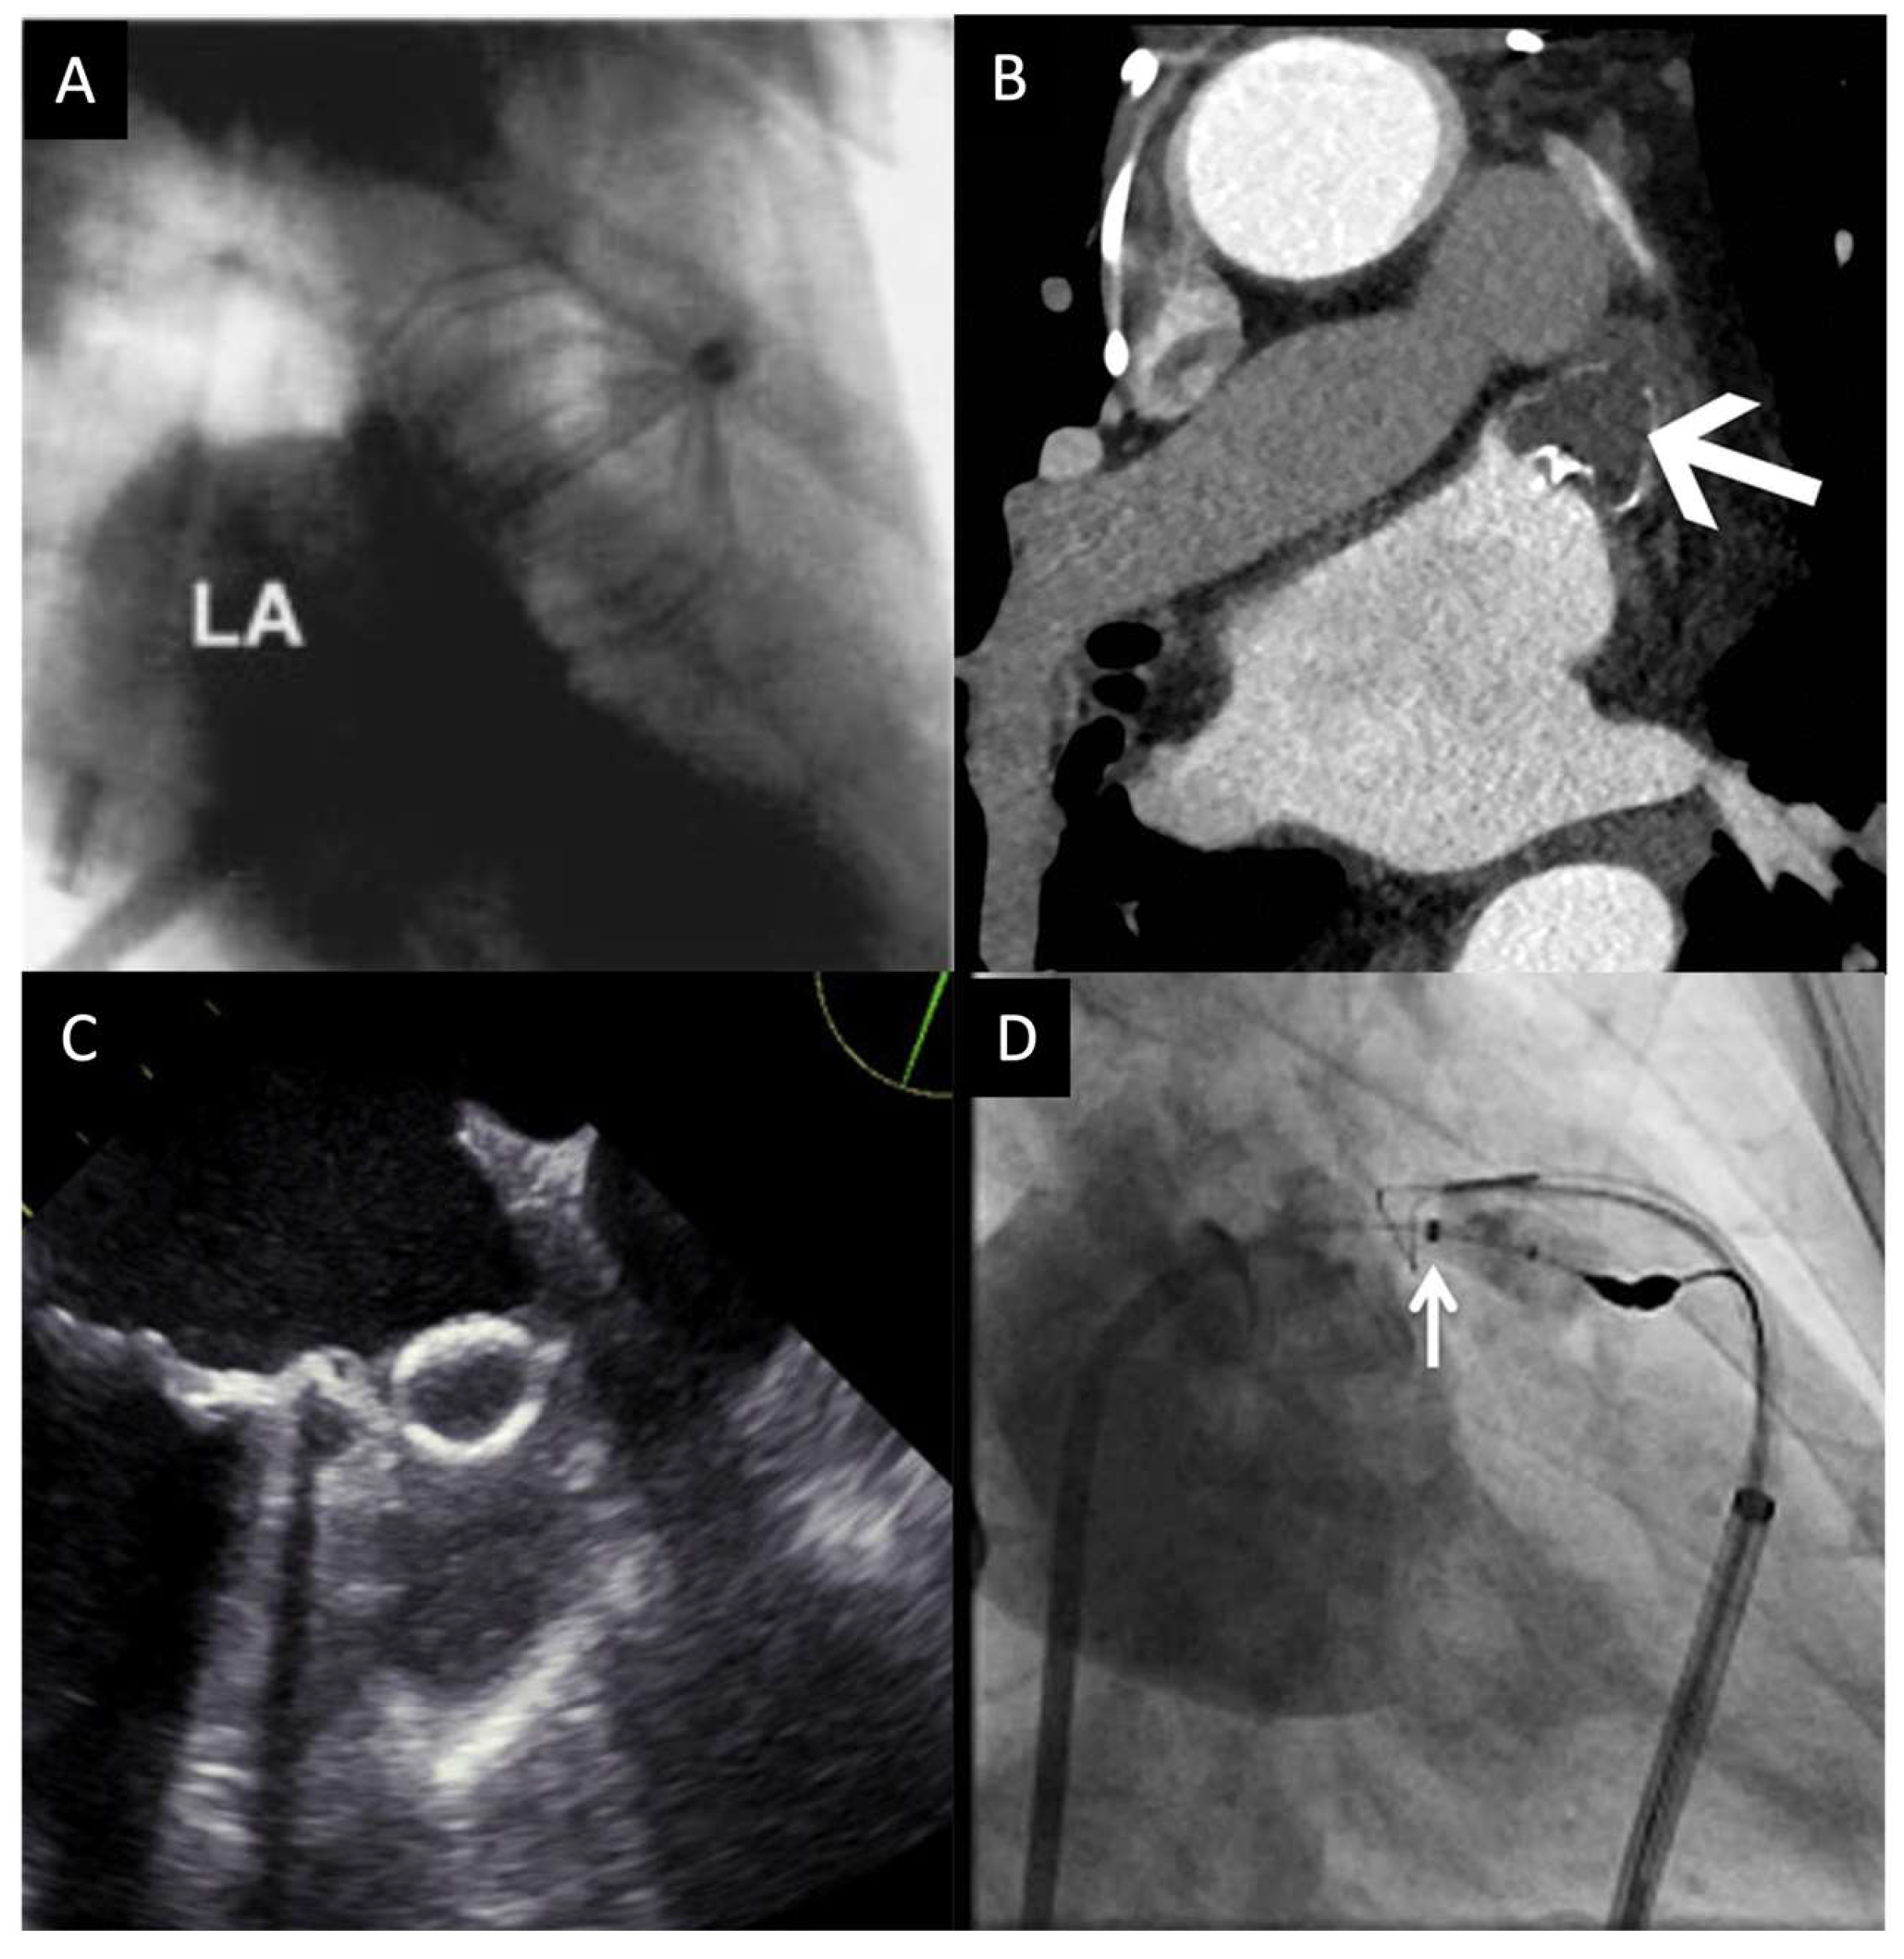

The currently approved devices for LAAO include WATCHMAN and Amplatzer Amulet. Patients who undergo left atrial appendage occlusion need to be suitable for short-term anticoagulation therapy, as the post-procedural guidelines indicate warfarin and anti-platelet therapy in the short term or indefinitely [54]. Percutaneous left atrial appendage occlusion has shown that it can be effective in reducing thromboembolic events in patients with an aversion to oral anticoagulation therapy. The devices used for the procedure are shown in Figure 2.

Figure 2.

Devices used for left atrial appendage occlusion. (A) Percutaneous left atrial appendage transcatheter occlusion system [55]. (B) WATCHMAN [56]. (C) Amulet [57]. (D) Lariat [58]. LA–left atrium.